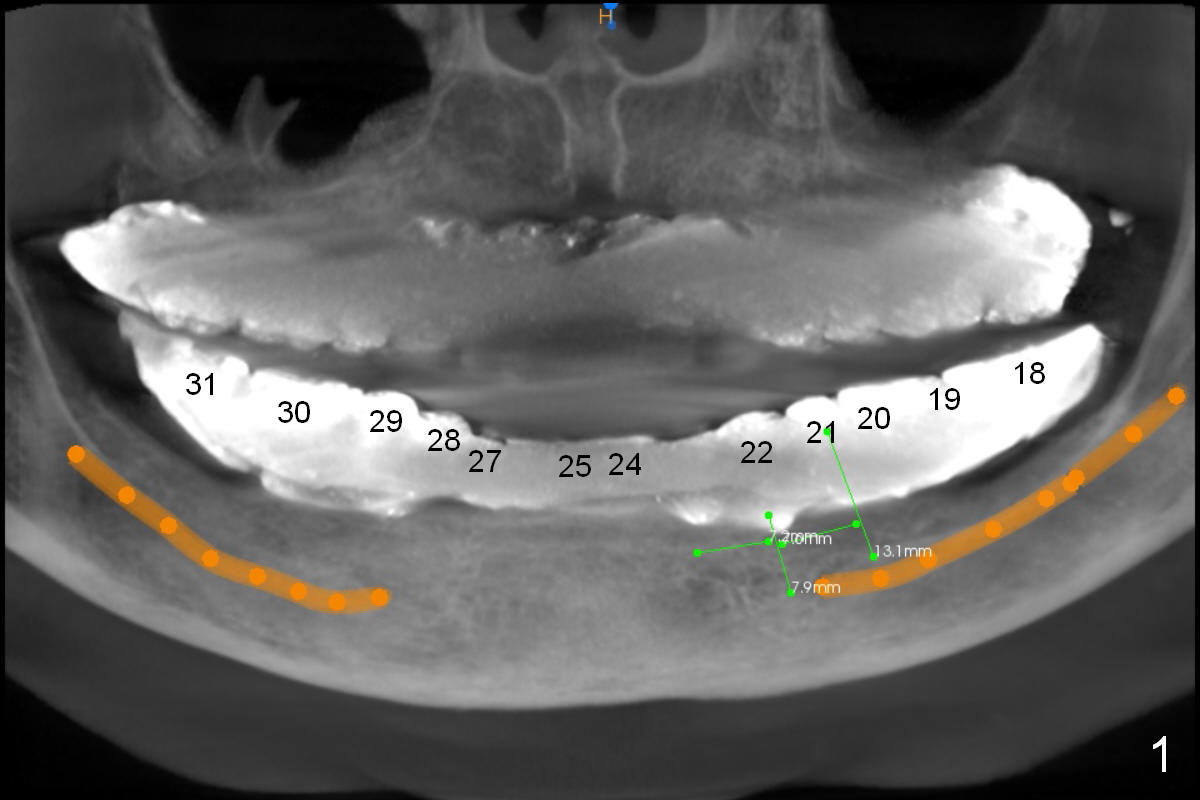

The patient wants to change unstable complete dentures to fixed ones. Because the problem of pain is associated with the lower left (Fig.1 the left Inferior Alveolar Nerve is more superficial), the lower arch will be reconstructed first. Totally 6 implants will be placed for bridges/crowns. Due to time constraint, four implants are placed at the 1st stage (#21, 22, 27 and 28 (Fig.4,5,8,9)); the lower denture will be retained immediately by ball abutments and soft relined. Two to three months later, two more implants will be placed (at #31 and 20, Fig.2,10). Note severe atrophy of the crest at #18 and 19 (Fig.11 and 12). If primary stability is achieved, a fixed immediate provisional will be fabricated.

In contrast to the upper arch, the bone density in the lower arch is high. The challenge is bone height. Short implants will be used (6 mm for #31 (Fig.2) and 8 mm for the majority of the others (at premolar and canine sites). If needed, extra implants will be placed at incisor sites (Fig.6,7 (implant can be longer)) and at #29 (Fig.3) . If a site is too small for a 3.8 mm 2-piece implant, a 1-piece one may be placed.